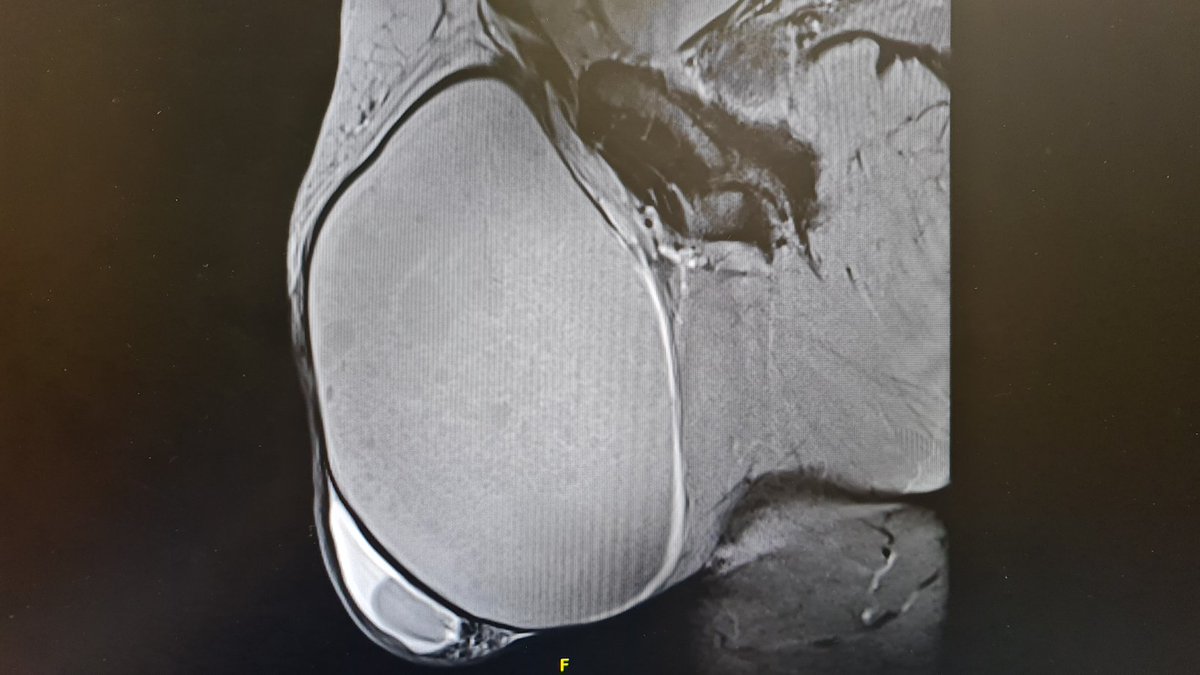

Urology resident at Fundacio Puigvert